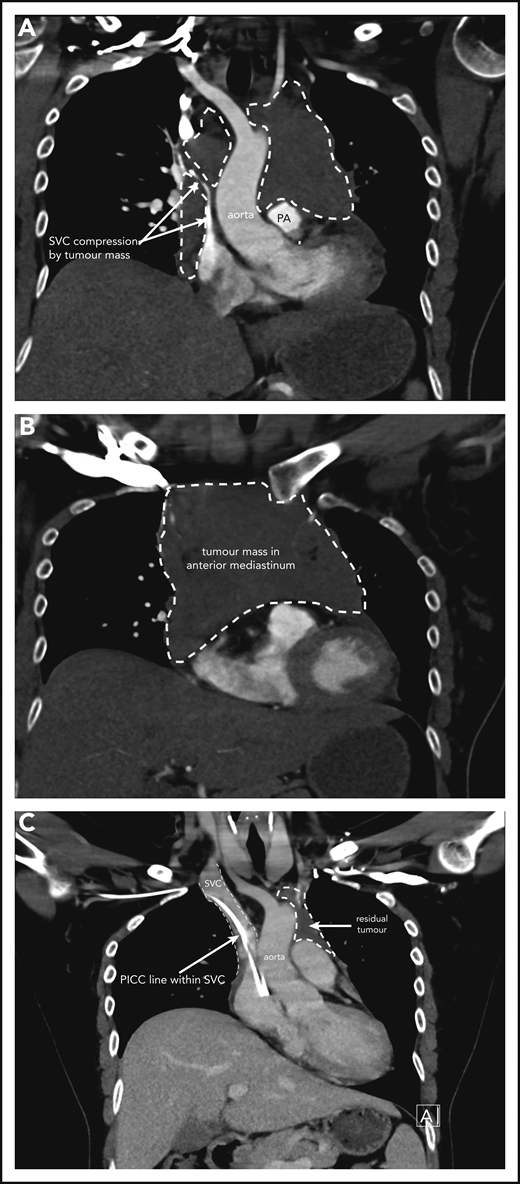

Case 1 of patient with primary mediastinal B-cell lymphoma presenting at 31weeks gestation. (A) Coronal section chest CT scan with contrast at diagnosis, pretreatment. Illustrates significant compression of SVC by tumor mass (within broken lines) on right and demonstrating extent of mass also on left superior to pulmonary artery (PA). (B) Transverse section chest CT scan with contrast at diagnosis, pretreatment. Illustrates extent of anterior mediastinal tumor mass. CT imaging suggested possible moderate-sized pericardial effusion found on echocardiography to be a small effusion. (C) Coronal section chest CT scan with contrast at completion of treatment. Normal caliber SVC with a peripherally inserted central catheter (PICC) line in situ. Small volume of residual tumor (within broken lines). Subsequent PET-CT scan demonstrated no activity confirming a complete metabolic response.

A 37-year-old woman, in her second ongoing pregnancy, presents to the emergency room at 30 weeks and 6 days (30+6 weeks) gestation with a history of chest pain and shortness of breath that woke her from sleep. She also has cramps in her right calf. She has been experiencing increasing shortness of breath and palpitations when mobilizing over a few weeks. She is a nonsmoker who drinks no alcohol. There are no concerns with her baby, and her first pregnancy and birth were uncomplicated. On examination, she is tachycardic at 120 beats per minute, normotensive with a blood pressure of 114/60 mm Hg, oxygen saturations of 97% on room air, and afebrile. Distended jugular veins are noted bilaterally, and she has no chest wall tenderness. Chest auscultation revealed crackles in the right lower zone. Heart sounds are dual with no murmurs. She has no lymphadenopathy, and abdominal examination reveals an enlarged uterus as expected for her dates with no other abnormalities. Complete blood count is normal. A comprehensive metabolic panel is normal other than an elevated lactate dehydrogenase (448 U/L; reference range, 120-250 U/L) and C-reactive protein (70 mg/L; reference range, 1-5 mg/L). The initial clinical concern for a pulmonary embolism prompted a computed tomography (CT)-pulmonary angiogram. This shows a large mediastinal mass measuring 11.5 × 8.3 × 8.3 cm causing significant obstruction of the superior vena cava and left main pulmonary artery and narrowing of the left upper lobe bronchi (Figure 1A-B). A small pericardial effusion is noted. Differential diagnosis includes lymphoma with other possibilities of thymic neoplasm, teratoma, or thyroid malignancy. A CT-guided biopsy of the mediastinal mass is performed and confirms focal areas showing proliferation of medium to large lymphoid cells. The large lymphoid cells are positive for CD20, CD79a, and PAX5, as well as BCL6, and have weak BCL2 staining. CD23 and CD30 show weak patchy positivity in the large cells and CD10, CD15, MUM1, cyclin D1, and Epstein-Barr virus in situ hybridisation (ISH) are negative. The Ki67 proliferative fraction is 60%. Fluorescence in situ hybridization studies reveal no rearrangement of MYC, BCL2, or BCL6. Pathologic features are consistent with a diagnosis of PMBCL.

The patient initially received high-dose steroids for treatment of her SVC syndrome once the diagnosis was made. She then received her first cycle of DA-EPOCH-R therapy at 33+3 weeks of gestation and tolerated it very well. Additionally, growth colony-stimulating factor was administered with no complications. An MRI of the chest was performed 2 weeks later and showed reduction in the size of the mediastinal mass to 8.6 × 4.5 × 5.4 cm with significant improvement in SVC and airway compression. Labor was induced at 35+5 weeks, and our patient had an uncomplicated vaginal birth to a healthy girl (birth weight, 2585 g) who had no neonatal complications. She received her second cycle of DA-EPOCH-R on day 22 as per the chemotherapy regimen without complication on the fourth postpartum day and subsequently completed a total of 6 cycles of therapy. CT and FDG-PET scans were done at completion of therapy, showing significant shrinkage of the mass on CT (Figure 1C) and complete metabolic response on FDG-PET, and she did not require consolidation mediastinal radiation. She remains in complete remission at last follow-up.